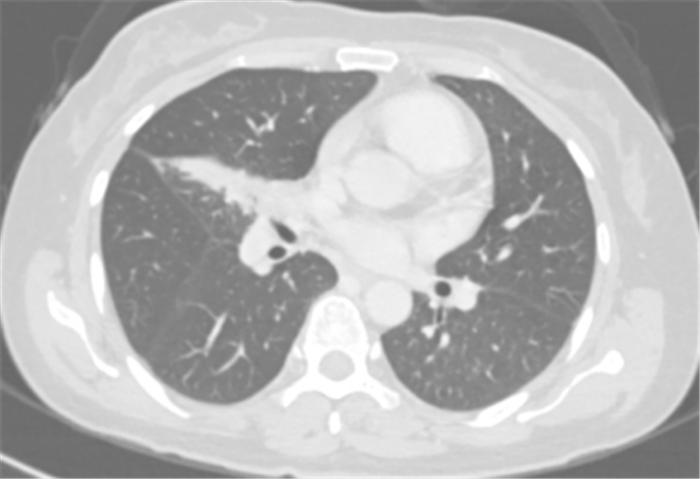

经过4个周期的治疗后复查发现:李女士的病灶明显缩小,实现了降低肺癌分期。

免疫联合化疗新辅助治疗4周期后胸部CT

肿瘤缩小降期,无疑为李女士打开了新的“生命之门”。经过评估后,心胸外科郭建极教授、阳诺博士团队为她行胸腔镜下右肺下叶切除术+纵膈淋巴结清扫术。

令人欣慰的是,术后病理提示送检肺组织为伴多量淋巴细胞浸润的大片坏死组织,未发现肿瘤残存,且淋巴结同样未见癌转移,术后病理分期达到了完全缓解。术后,李女士继续接受辅助免疫单药维持治疗,不仅安全而且耐受性良好。